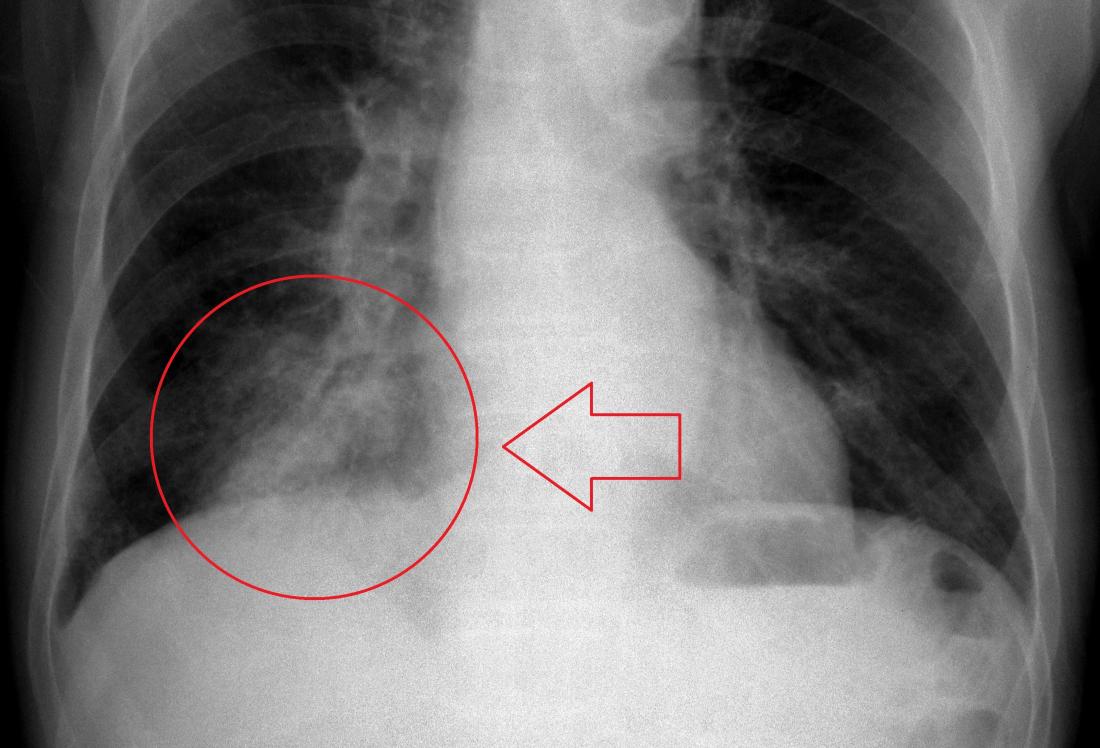

Üşüme- titreme, 39- 40 °C'ye varan yüksek ateş, öksürük, kirli, iltihaplı (yeşil, sarı, pas rengi) balgam çıkarma ve yan ağrısı olabilir. Bazı pnömoni türlerinde ise sinsi başlangıç olur. Birkaç gün devam eden iştahsızlık, halsizlik, eklem ve kas ağrılarını takiben kuru öksürük, ateş yükselmesi, bulantı, kusma, baş ağrısı gibi belirtiler olabilir. Bu şikayeti olan hastalar mutlaka doktora başvurmalıdır. Pnömoni ihmal edilmemesi gereken bir sağlık sorunudur. Erken teşhis edilmesi ve gecikmeden tedaviye başlanmasının ölümleri azalttığı bilinmektedir. Hastanın yakınmaları pnömoni'yle uyumlu ise genellikle yapılan muayene ve akciğer röntgenindeki bulgularla teşhis konulabilir. Gerekirse kan ve balgam tahlilleri yapılabilir.